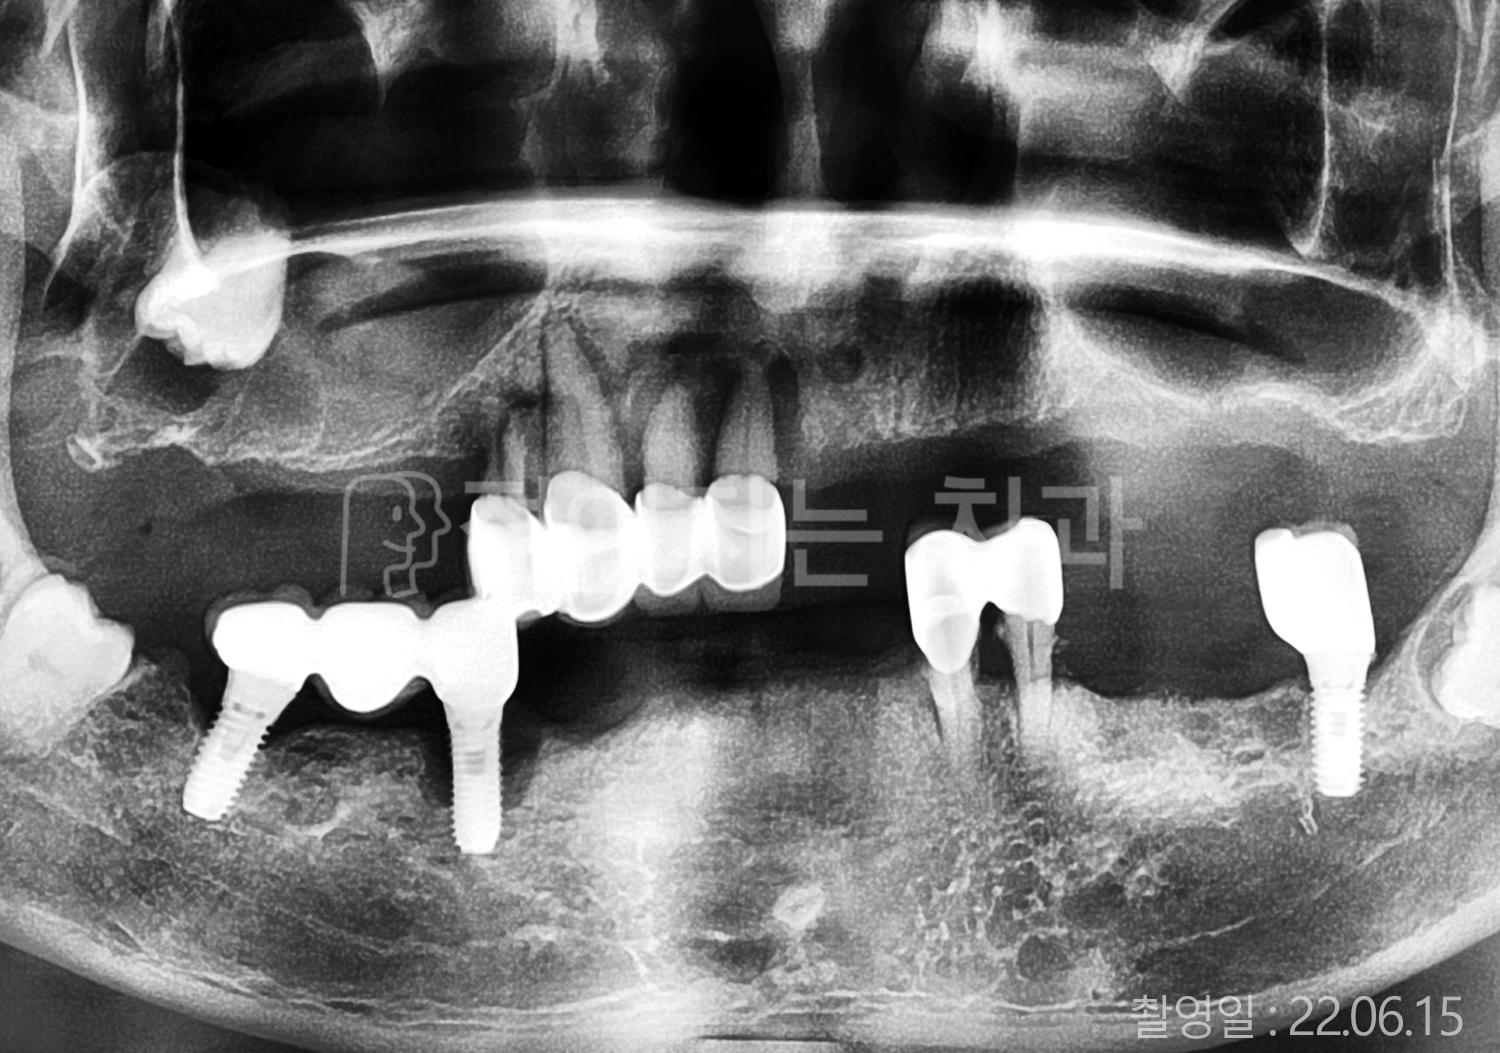

• 50대 고혈압, 당뇨 전체치아 10개 이상 임플란트

• 40대 전체치아 10개 이상 임플란트

• 60대 전체치아 10개 이상 임플란트